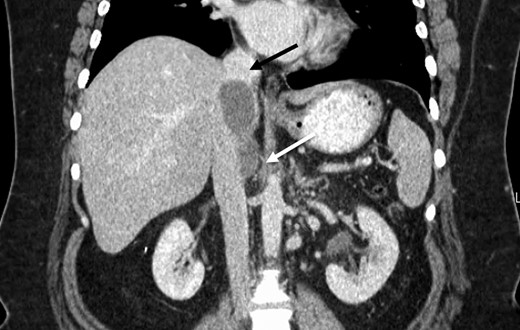

The patient was followed with serial imaging for the next 6 years when a recurrent mass was noted in the retrohepatic IVC. The tumor originated just above the renal veins and extended into the hepatic veins (Fig. 1). At this point she was referred to the University of Colorado for further evaluation. Her work-up included CT angiogram and an magnetic resonance imaging (MRI) of her liver. The CT showed a 4 cm by 3 cm intracaval mass at the level of the IVC-hepatic vein confluence. An additional 9-mm nodular mass was noted within the cava raising the possibility of dis-contiguous disease (Fig. 1). Following appropriate preoperative counseling, the patient was taken to the operating room for surgical resection. Extensive lysis of adhesions was performed from a large midline incision. Following complete mobilization of the liver, and control of the suprahepatic and infrahepatic cava, she underwent segmental resection of the IVC between the renal and hepatic veins with reconstruction using a 24-mm Dacron tube graft. All grossly visible tumor was removed (Fig. 2).

Preoperative CT identifying a smooth, well-circumscribed mass within the IVC arising superior to the right renal vein long (white arrow) and terminating just prior to right hepatic take-off (black arrow).